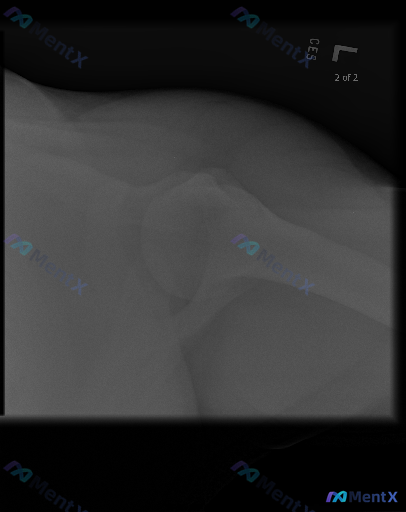

整理到一份很有意思的左肩影像资料: - 影像报告结论是:所见骨骼结构完整,关节对位良好,未见明显骨折、脱位、明显退行性变或软组织钙化征象 - 但同时又明确提示:存在异常 这种「症状或临床提示阳性,但X光平片完全正常」的情况,其实在门诊挺常见的,但也很容易踩坑。 大家第一反应会先往哪个方向考虑?下一步...